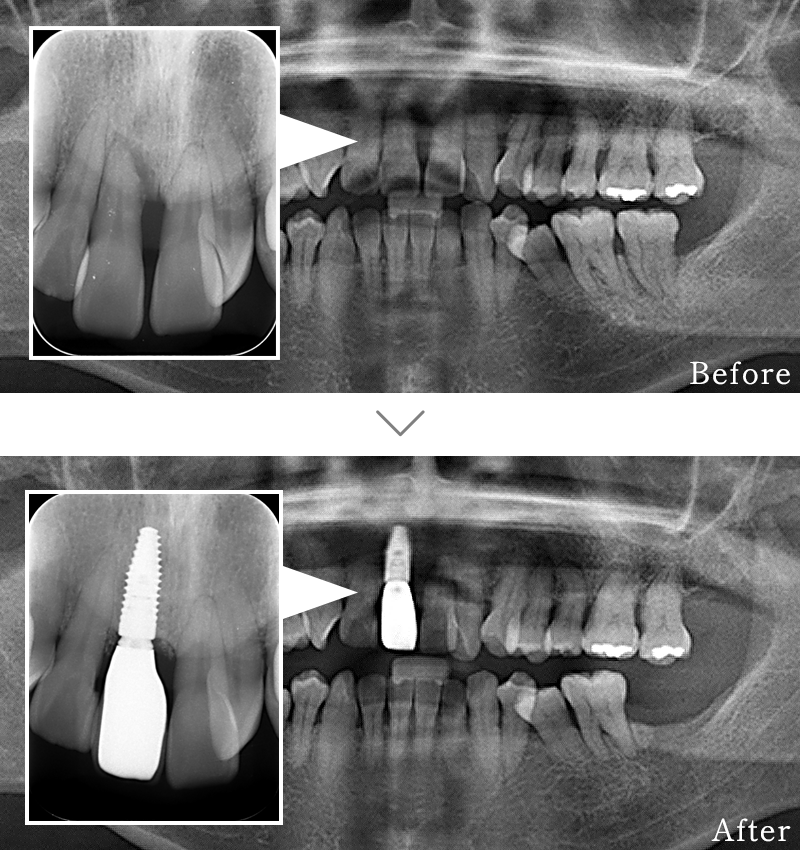

CASE3

主訴 歯の本数が少なく、全体的に隙間があいている。

治療法 矯正治療後に上にインプラント2本使い、噛み合わせと見た目を回復しています。インプラント部位は骨が薄かったため、造骨処置(GBR)と歯肉移植(CTG)を行なっています

治療期間 10ヶ月

※矯正治療の期間は含まれておりません。

費用 CT:16,500円(税込)

+ インプラント治療:1,051,600円(税込)

+ 造骨処置(GBR):176,000円(税込)

合計:1,244,100円(税込)

※矯正治療費は含まれておりません。

副作用

• 歯周病に感染・発症し重度に進行するとインプラントが抜けてしまうことがあります。

• 手術後は数日間腫れが出る場合があります。

• 歯肉移植時は、採取部位からの出血が数日続くことがあります。